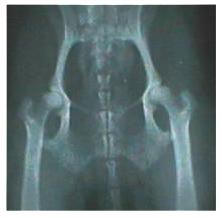

Above are examples of hip x-rays of two different Cavaliers. If

you compare the two you can see that the hip sockets on the

right x-ray are not as deep as those on the left x-ray,

therefore the femoral heads do not sit as deeply into the

sockets—more of the femoral head is left out of the socket.

Also, in the dysplastic x-ray, you can see the circled hip is

much worse than the other hip. The end of the femoral head is

already worn down. Because of stress, the area pointed to behind

the femoral head has filled in so much the indentation is nearly

gone. Compare this to the other three hips that have good

indentation behind the femoral head. NOTE: the dog with the

dysplastic hips showed NO signs of hip dysplasia when walking

or running. The x-ray was taken only because the owner wanted to

make sure the dog did not have hip dysplasia before it was bred.

Since the dog does have hip dysplasia, the breeder decided not

to breed the dog. Also, BOTH parents are OFA clear of hip

dysplasia, and so is the one other sibling whose hips have been

x-rayed and sent to OFA.